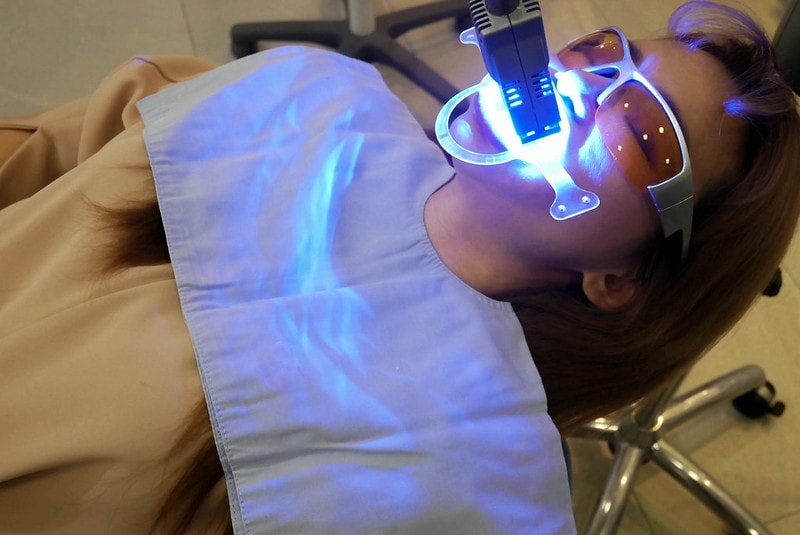

因為我這天也順便預約了牙齒冷光美白

療程開始前人美心又美的女醫生

除了清潔還順便幫我洗了一下牙

原本牙齒愛喝咖啡所以呈現黃黃的狀態

其實我都有陸續在保養

但因為每天都喝咖啡還是難免~

只能偶爾來進場維修一下哈哈

原本已經很久沒做冷光美白

記憶中的冷光美白超痠軟

還好這邊診所牙齦隔離保護做得很徹底

美白藥劑也很溫和不刺激

真的比我上一次做不那麼痠很多

冷光美白會清潔之後塗上藥劑照光

基本上美白的效果非常好

如果你是以前從來沒有美白過牙齒的人

可以一次白個五到六個色階

我算是平常有在居家護理的人

所以我的牙齒已經算沒那麼黃的

但冷光美白一做完

馬上就白到了自然牙齒最白的色號A1色喔

愛喝茶跟愛喝咖啡的人真的應該來日常護理一下

做完超有成就感~也會比較愛笑<